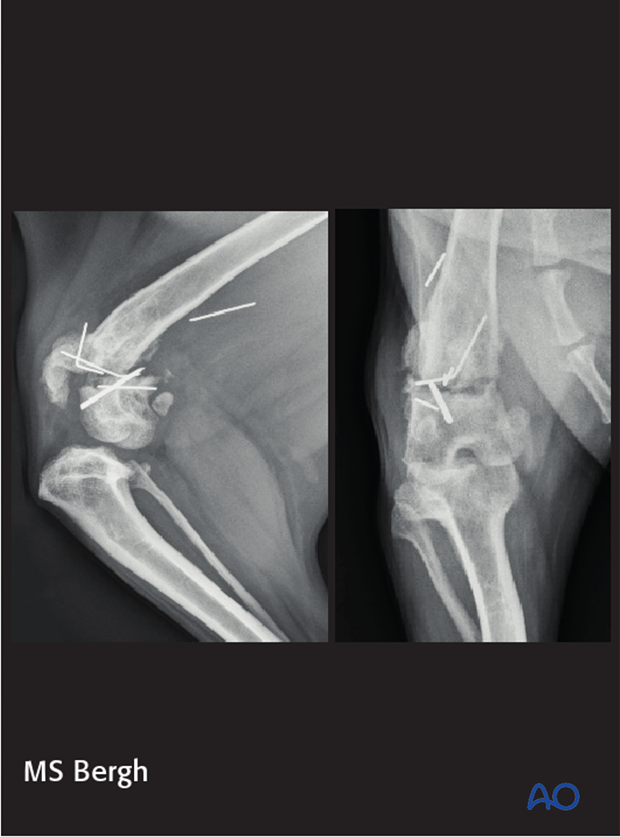

Mary Sarah Bergh

Complications in distal femoral fractures